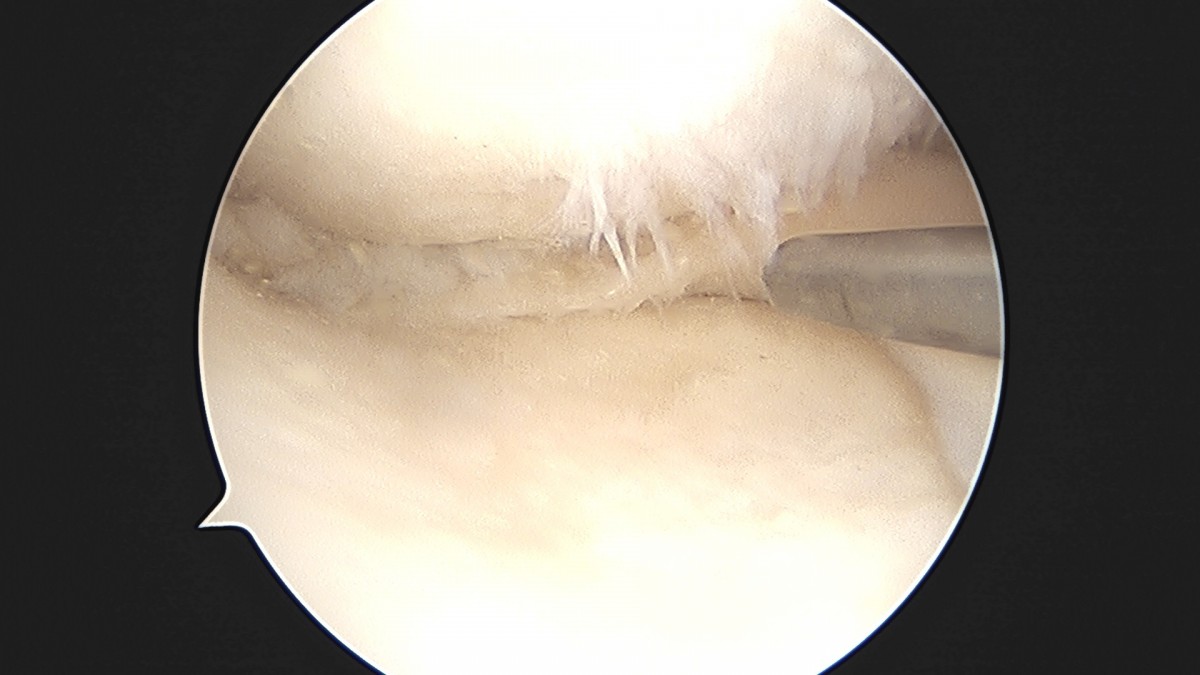

이재상원장님 무릎 반월상 연골판 절제술 박민O 환자

작성자 최고관리자 댓글 0건 조회 382회 작성일 25-09-16 15:46